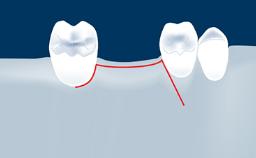

- describe the indications for digital guides in SFE